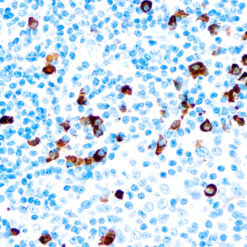

CD7 is expressed by most peripheral blood T cells, NK cells, and all thymocytes. It is one of the earliest surface antigens on T and NK-cell lineages. The antibody is a useful aid for classification of T-cell malignancies.

| Clone | CBC.37.8 |

| Immunogen | a T lymphoblastoid cell line, established from a patient with acute lymphoblastic leukemia |